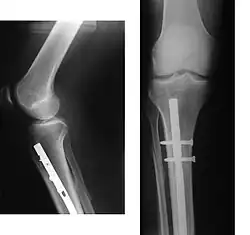

Correcção cirúrgica de fratura proximal da tíbia, através de vareta e parafusos.

A cirurgia tem por objectivo restabelecer o alinhamento normal do osso, e manter esse alinhamento até a reparação da fratura. Permite também corrigir algumas lesões das partes moles, em especial vasos sanguíneos que possam ter rompido.

O restabelecimento da continuidade óssea por meio cirúrgico (osteossíntese) pode ser feito com recurso a várias técnicas, habitualmente com a utilização de placas e parafusos, varetas endomedulares ou Fios de Kirschner.